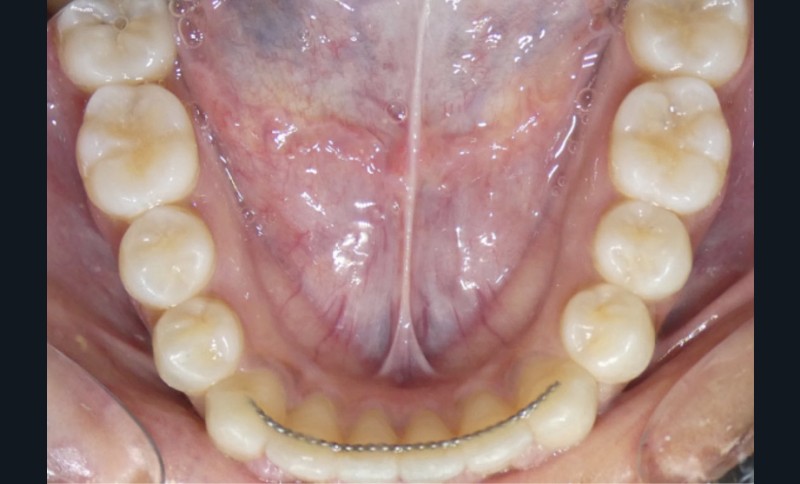

Diagnostic (fig. 1 et 2)

À l’examen intra-oral, les arcades sont paraboliques, la courbe de Spee est normale. On remarque l’absence de la 23 sur l’arcade ainsi que la persistance de la 63. La patiente présente une Classe II partielle molaire et canine subdivision droite, ainsi qu’une insuffisance de recouvrement. Un léger encombrement incisif mandibulaire est présent, ainsi que des diastèmes maxillaires avec une dysmorphie dento-dentaire de 12 et 22.

La radiographie panoramique permet de confirmer l’inclusion de la 23, apicale aux dents 21 et 22, ainsi que la présence d’un odontome en apical de la 63. Ces éléments nécessitent la réalisation d’un CBCT.